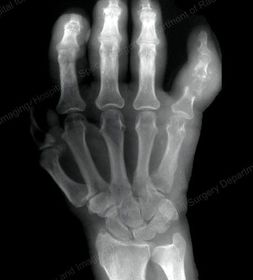

| PA Hand | distal phalynxes are bent flatten hand to true PA *should be equal concavity on all digits* |

| PA Hand | obliqued - fingers are not equally concave on both sides distal metacarpals are overlapped |

| Oblique Hand | Overly obliqued - metacarpals superimposed joint spaces closed - fingers bent |

| Oblique Hand | MCP joints superimposed - fingers too close together *underexposed |

| Oblique Hand | joint spaces closed hand overly obliqued MCP joints superimposed |

| Fan Lateral Hand | phalanges are superimposed and not well visualized patient's hand is externally rotated |

| Fan Lateral | patient's 2nd digit is bent - closed joint space hand is internally rotated |

| Fan Lateral | patient's metacarpals are not superimposed - hand is externally rotated distal phalanx's are bent - joint spaces closed not truly lateral |

| PA Hand | ANATOMY: entire hand including 1'' of distal radius and ulna CRITERIA: equal concavity on either side of digits digits separated with no superimposition open joint spaces POSITIONING: CR perpendicular @ 3rd MCP joint |

| Oblique Hand | ANATOMY: entire hand including 1'' of distal radius and ulna CRITERIA: digits more concave to one side minimal overlap of 3rd-5th metacarpal shafts separation of the 2nd and 3rd metacarpals POSITIONING: CR perpendicular @ 3rd MCP joint |

| Lateral Hand | ANATOMY: entire hand including distal 1'' of radius and ulna superimposed CRITERIA: metacarpals and distal radius/ulna are superimposed thumb is free of superimposition *thumb in lateral position* open joint spaces POSITIONING: CR perpendicular @ 3rd MCP joint LAT Extension: foreign body localization LAT Flexion: phalanges |